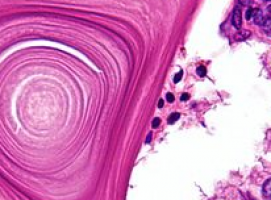

However, most importantly, they found that NOX1/ROS signalling caused gastric epithelial stem cells to multiply uncontrollably, resulting in tumour formation.

NOXO1 is a component of the NOX1 complex, which produces tissue-damaging molecules called reactive oxygen species (ROS). ROS, or more accurately, the oxidative stress caused by these molecules, can result in mutations in the DNA of stomach cells, leading to tumour formation.

Inflammation caused by H. pylori infection also produces ROS, increasing oxidative stress in the stomach.